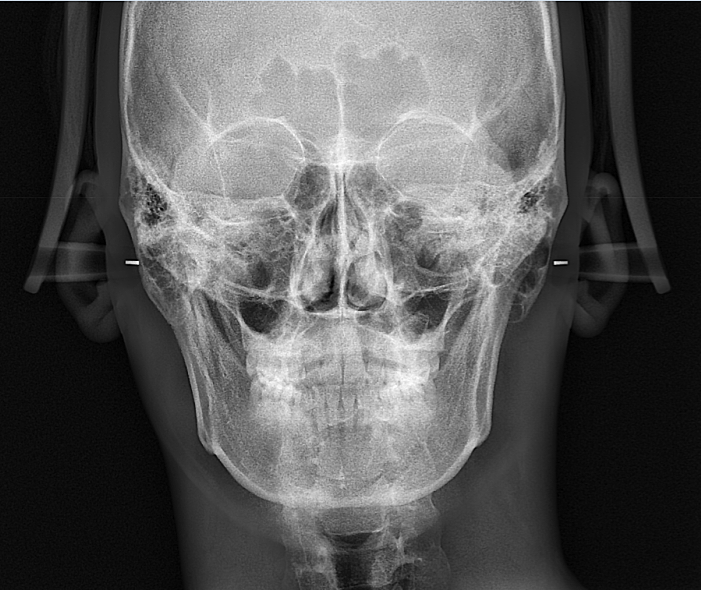

파노라마 사진보고 비중격만곡증 있는지 확인 가능한가요?

현재 파노라마 뷰 및 두개골 xray사진만으로는 정확히 비중격 만곡증을 확인할 수 없습니다. 직접 진료를 통해 확인하거나 CT 사진을 확인하는 것이 정확한 진단에는 도움이 될 수도 있으니 해당과 전문의에게 먼저 진료를 받으시는 것이 좋겠습니다.

비중격 만곡은 X-ray 파노라마 사진만으로는 감별이 어렵습니다.

비중격이 우측으로 치우쳐 비강의 크기가 달라보이지만 실제 신체진찰도 함께 병행되어야 감별이 가능합니다.

엑스레이 검사를 통해서는 비중격에 대한 정확한 평가가 가능하지 않습니다. 올리신 엑스레이 사진에서는 딱히 비중격만곡증을 의심할만한 소견은 보이지 않지만 그렇다고 하여 완전히 배제할 수는 없습니다. CT와 같은 더 정밀한 검사를 확인할 필요가 있습니다.